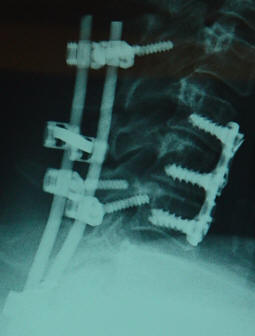

24-MAY-2008  AMAL AL-FAQIR  48 YEARS  SLIPPED

UPPER SCREWS IN THE POSTERIOR CERVICAL FUSION DEVICE. |

Preoperative X-rays showing the construct. | Anamnesis:

|  | The patient came to the

clinic 05-February-2008 still complaining of

agonizing neck pain and unable to move her left

upper limb. CT-scan performed 05-December-2007

showing good alignment of the four lower screws,

but with partial slipping of the upper two

screws. She was advised to keep in medications

and protelose to accelerate the bony fusion. |

|  | The patient was sent for

CT-scan of the cervical spine and simple

cervical X-rays, which confirmed further

slipping of the upper screws. |